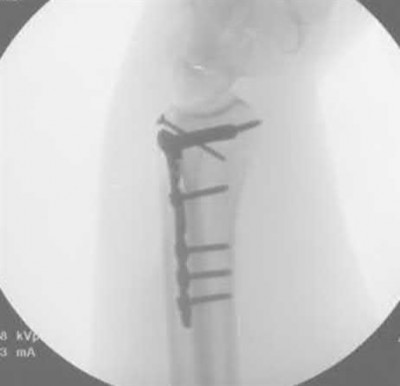

Figure A demonstrates a displaced subtrochanteric femur fracture with an intact lesser trochanter. The pull of iliopsoas on the lesser trochanter as well as the intact external rotators and gluteal musculature results in the the proximal fragment being in a flexed and externally rotated or abducted position (the most common post operative deformity). Reduction manuevers must be biologically friendly but also counteract the flexion/abduction moment. Lundy's review article discusses evaluation and treatment of subtrochanteric fractures. The review article details the various implants often used which include 95 degrees plates, femoral reconstruction nails, or trochanteric femoral nails with interlocking options. Lundy's article discourages the use of the 135 degree screw and side plate combo due to high failure rates in these fracture patterns. Bedi et al also review treatment of these fractures and discuss common

problems of malunion, nonunion, and implant failure. The article reviews reduction techniques that are soft tissue friendly, as well as the use of appropriate implants in these fracture types.